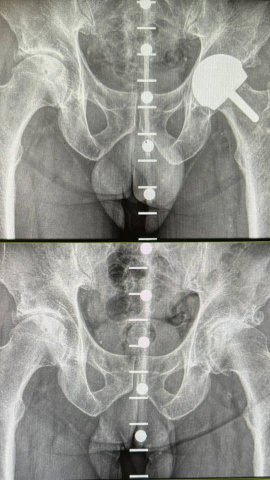

Esta técnica está especialmente diseñada para prótesis en pacientes jóvenes y deportistas